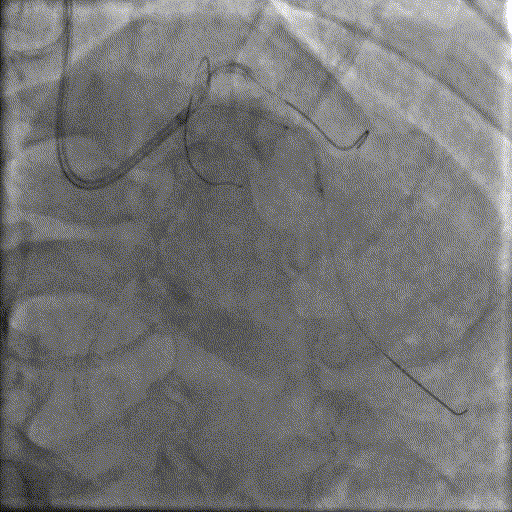

手术过程

导丝到位

当指引导管冠脉开口到位后,选择三根对应导丝分别送入LCX、OM1、OM2远端。

OM2优先处理:

球囊预扩

当导丝通过病变后其他器械无法通过病变,此时选择不同尺寸的小球囊逐级预扩张病变,复查造影狭窄减轻不明显。为了解血管真实情况,遂启用IVUS检查。

术前腔内影像学IVUS指导

IVUS提示血管可见钙化明显,为360°环形钙化。遂考虑启动IVL治疗。

冲击波球囊治疗

2.5*12mm@4atm 冠脉血管内冲击波导管反复进行4个周期治疗,复查造影提示狭窄减轻。

支架植入并后扩

于OM2-LCX远端植入一枚药物洗脱支架,经非顺应性球囊后扩张支架,复查造影提示支架贴壁良好,未见夹层、血肿。